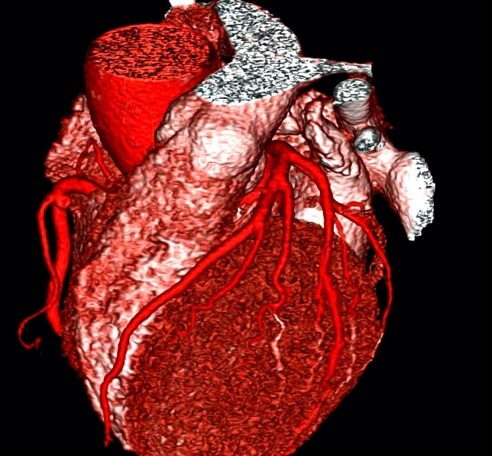

While coronary artery calcium scoring provides an overall assessment of the extent of atheroma (fatty deposits), it does not provide anatomical information, the localisation or severity of any lesions. This is provided by the CT Coronary Angiogram. In a small percentage of patients, the calcium score can be low or even zero but the presence of atheroma (“soft plaque”) can still exist and therefore expose the patient to CHD events. The CT Coronary Angiogram can depict the presence and extent of coronary atheroma in patients with low and elevated calcium scores.

The application of CTCA has been endorsed by NICE, with their 2012 recommendation that it should be the initial investigation for patients with stable chest pain.

The high sensitivity of CTCA has resulted in it being increasingly used as a screening tool for CHD, particularly as our latest software has reduced the radiation dose to approximately that of a calcium score. Its other advantages include;